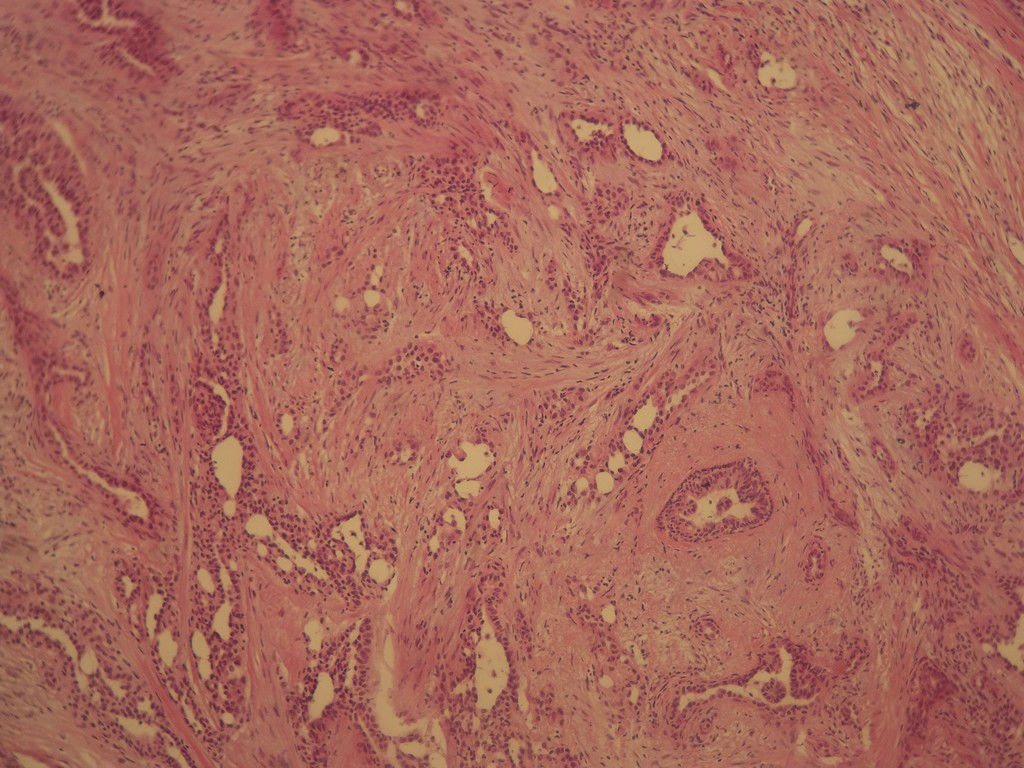

今天的一例术中冰冻。女,49岁,乳腺肿块。人气不旺,换个标题

腺病?癌?其他?(12楼常规,24楼免疫组化及会诊结果)图1

标签:浸润性导管癌 分泌癌 硬化性腺病

导管是乎可见双层上皮,部分上皮增生并有一定异型,考虑硬化性腺病,待石蜡。

导管可见双层上皮,部分上皮增生并有一定异型,考虑硬化性腺病

腺体与腺体之间的对比差异太大,不放心,不除外是癌,如果是我的病例,再次取材冰冻

后取的恶性特征明显多了,神经内分泌癌?

浸润性导管癌

浸润性导管癌。冰冻切片的诊断是很困难,直接诊断癌风险很大,但是在明显正常的导管间这种成片、成巢有腔的细胞团块也不是良性的表现,有的还似乎有围绕正常导管生长的倾向。诊断ADH还可以,但是不能归到任何一种DCIS的生长方式里。这例值得我好好学习。